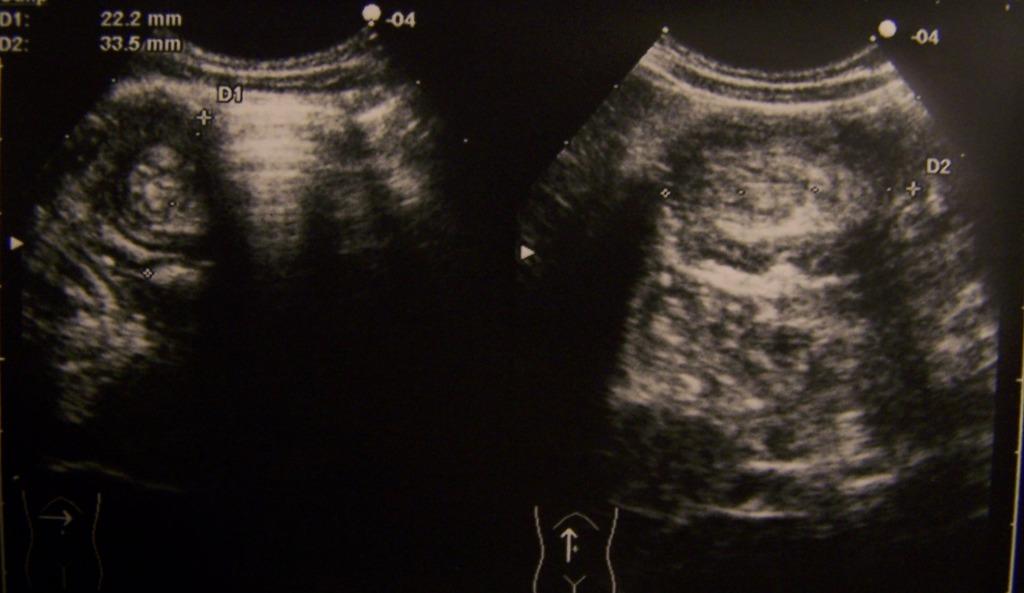

Ecograficamente l�invaginazione si presenta in scansione traversa all�asse dell�intestino (Figura 3), solitamente all�ipocondrio destro, come una massa rotondeggiante con aspetto a bersaglio, con parete esterna ipoecogena e ispessita a causa dell�edema parietale, e con area centrale iperecogena (Doughnut-like pattern). Nella periferia della massa � pi� comune l�immagine ad anelli concentrici con gli anelli esterno e interno ipoecogeni e l�anello intermedio iperecogeno.

Figura 3. Scansioni traversa e longitudinale in ipocondrio dx: evidenza di due immagini a bersaglio da attribuirsi a invaginazione ileo-colica che interessa un lungo tratto di intestino (ileo, colon ascendente e traverso).

Tali anelli corrispondono rispettivamente a parete esterna, parete interna e interfaccia fra le due pareti (target-like pattern).

In scansione longitudinale � possibile visualizzare due strati esterni ipoecogeni (parete esterna dell�invaginato) e due interni ipoecogeni (parete interna) separati fra loro da 3 interfacce iperecogene. L�aspetto dell�invaginato perde queste caratteristiche quando la stasi venosa eccessiva comporta edema imponente e/o ematoma sottosieroso. In tal caso � possibile apprezzare una massa solida senza evidenza di stratificazione.